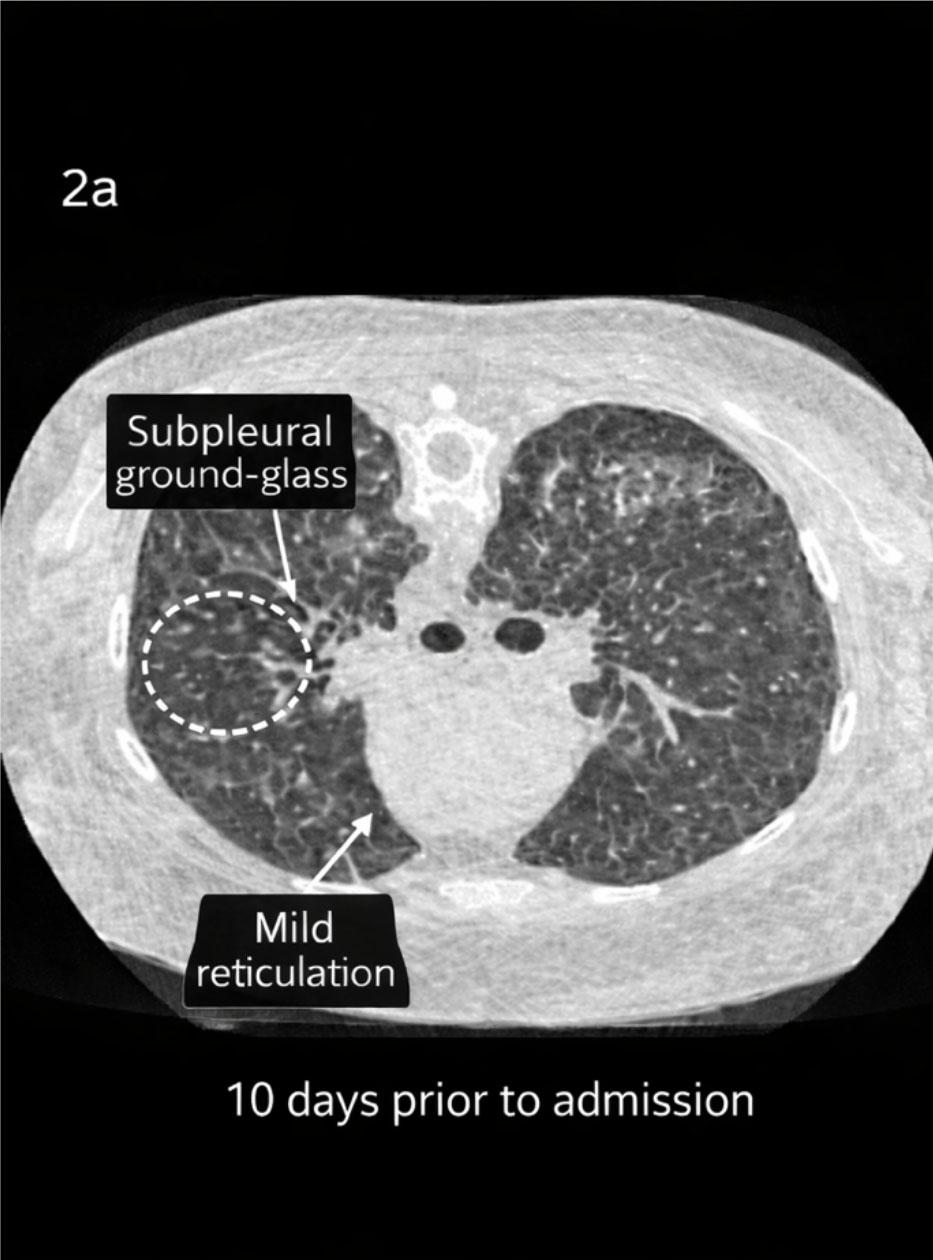

Figure 2a: